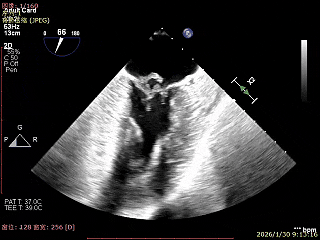

术前超声评估

经胸超声报告提示:患者二尖瓣2区及3区前叶关闭时脱入左房,二尖瓣重度反流(MR 4+),患者LA前后径约52mm,LVEDD约68mm,LVESD约42mm,EF值:65%,经胸超声测二尖瓣瓣口面积约6.1cm2,主动脉瓣无冠瓣脱垂并中重度反流,三尖瓣中度反流,估测中度肺动脉高压。

经食道超声精细化测量:肺静脉逆流,房间隔可穿刺高度约4.2cm,Flail宽度约21mm,Flail高度约8mm,Flail Gap约4mm, 3区AML长约23mm、PML长约12mm、2区AML约32.2mm,PML约16mm。

Bicomm切面看2区脱垂

上Color,可见反流主要来自于3区

X-Plane切面切1区未见明显异常

1区上Color,未见反流来源

X-Plane切面切2区可见前叶Flail

2区上Color,可见反流来源

X-Plane切面切3区可见前叶脱垂

3区上Color,可见反流来源

3D Enface 2区及3区前叶脱向左房

3D Enface 可见反流由2区3区从前后冲出

房间隔可穿刺高度约4.2cm

Flail宽度约21mm,Flail高度约8mm

经胸短轴测得瓣口面积约6.1cm2

3区前叶长度约22mm,后叶长度约11.6mm

2区前叶长度约32.2mm,后叶长度约16mm

2区Flail Gap约4mm